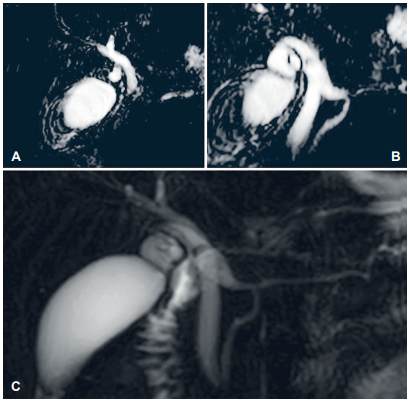

Adicionalmente fue valorada por el servicio de gastroenterología, quienes consideraron necesario realizar pancreatoscopia más litotripsia por spyglass por la pancreatolitiasis. En la colangiorresonancia (Figura 2) se evidenció dilatación del conducto cístico, con imagen hipointensa en su interior que sugería la presencia de cálculo, con terminación en el conducto pancreático; dilatación del conducto pancreático de Santorini a nivel de la papila menor, sin cálculo en su interior; vía biliar intrahepática y colédoco levemente dilatados. Dada la posible alteración anatómica de los conductos pancreáticos sin cálculos en su interior, se canceló la pancreatoscopia más litotripsia y, para evaluar con mayor claridad la anatomía, se solicitó una resonancia con contraste hepatoespecífico, con la que se descartó la presencia de cálculos y los hallazgos adicionales sugirieron un posible Santorinocele.

Se presentó el caso en junta multidisciplinaria y por la anatomía no clara se decidió realizar colangio pancreatografía retrograda endoscópica (CPRE) con fin diagnóstico. Se identificó una variación anatómica en la cual el conducto cístico drenaba en el conducto pancreático principal, denominada posible vesícula pancreática. Finalmente, se llevó a exploración quirúrgica por laparoscopia, se disecó el hilio hepático logrando ventana de seguridad de Straberg 10, pero con visualización de una estructura tubular de inserción baja al conducto cístico. Al realizar la colangiografía intraoperatoria no se logró aclarar adecuadamente la anatomía de la vía biliar, se identificaron dos conductos biliares distales, sin poder definir su terminación (Figura 3), por lo que se decidió convertir a cirugía abierta dada la complejidad del caso y la duda anatómica.

Se hizo disección circunferencial anterógrada de la vía biliar extrahepática, identificando un conducto colédoco accesorio (Figura 4). Mediante una nueva colangiografía intraoperatoria no fue posible determinar cuál era el conducto principal y cuál el accesorio para resecarlo. Teniendo en cuenta estos hallazgos y el alto riesgo de desarrollar colangiocarcinoma en el futuro por la variante anatómica, la inflamación y el dolor crónico, se decidió resecar los conductos biliares distales y realizar reconstrucción biliopancreática. Se procedió a la colecistectomía, protegiendo el conducto hepático derecho accesorio que terminaba en el cístico; se seccionó el colédoco proximal posterior a la llegada del cístico, con disección caudal del mismo, donde se observó una bifurcación, configurándose una duplicación del colédoco tipo II. La porción distal de ambos colédocos se disecó, seccionó y se cerraron los muñones lo más cercano al páncreas; finalmente se realizó una hepaticoyeyunostomía en Y de Roux. El reporte final de patología informó un conducto colédoco y conducto accesorio con fibrosis e inflamación crónica, sin evidencia de malignidad.